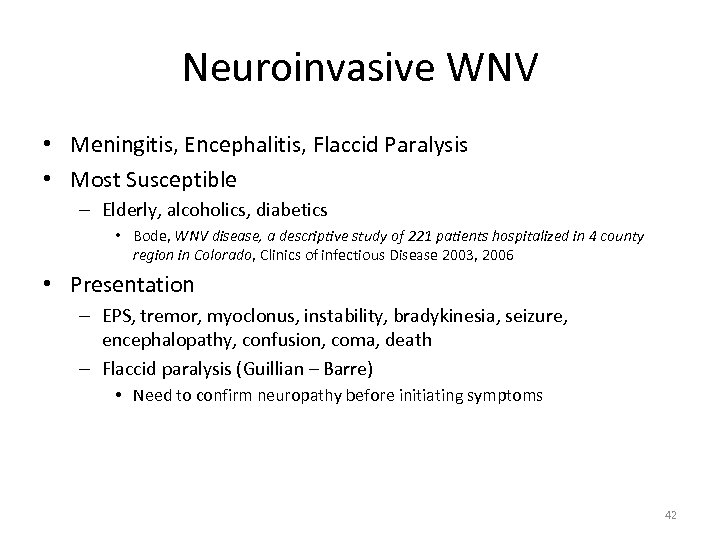

Neuroinvasive WNV • Meningitis, Encephalitis, Flaccid Paralysis • Most Susceptible – Elderly, alcoholics, diabetics • Bode, WNV disease, a descriptive study of 221 patients hospitalized in 4 county region in Colorado, Clinics of infectious Disease 2003, 2006 • Presentation – EPS, tremor, myoclonus, instability, bradykinesia, seizure, encephalopathy, confusion, coma, death – Flaccid paralysis (Guillian – Barre) • Need to confirm neuropathy before initiating symptoms 42